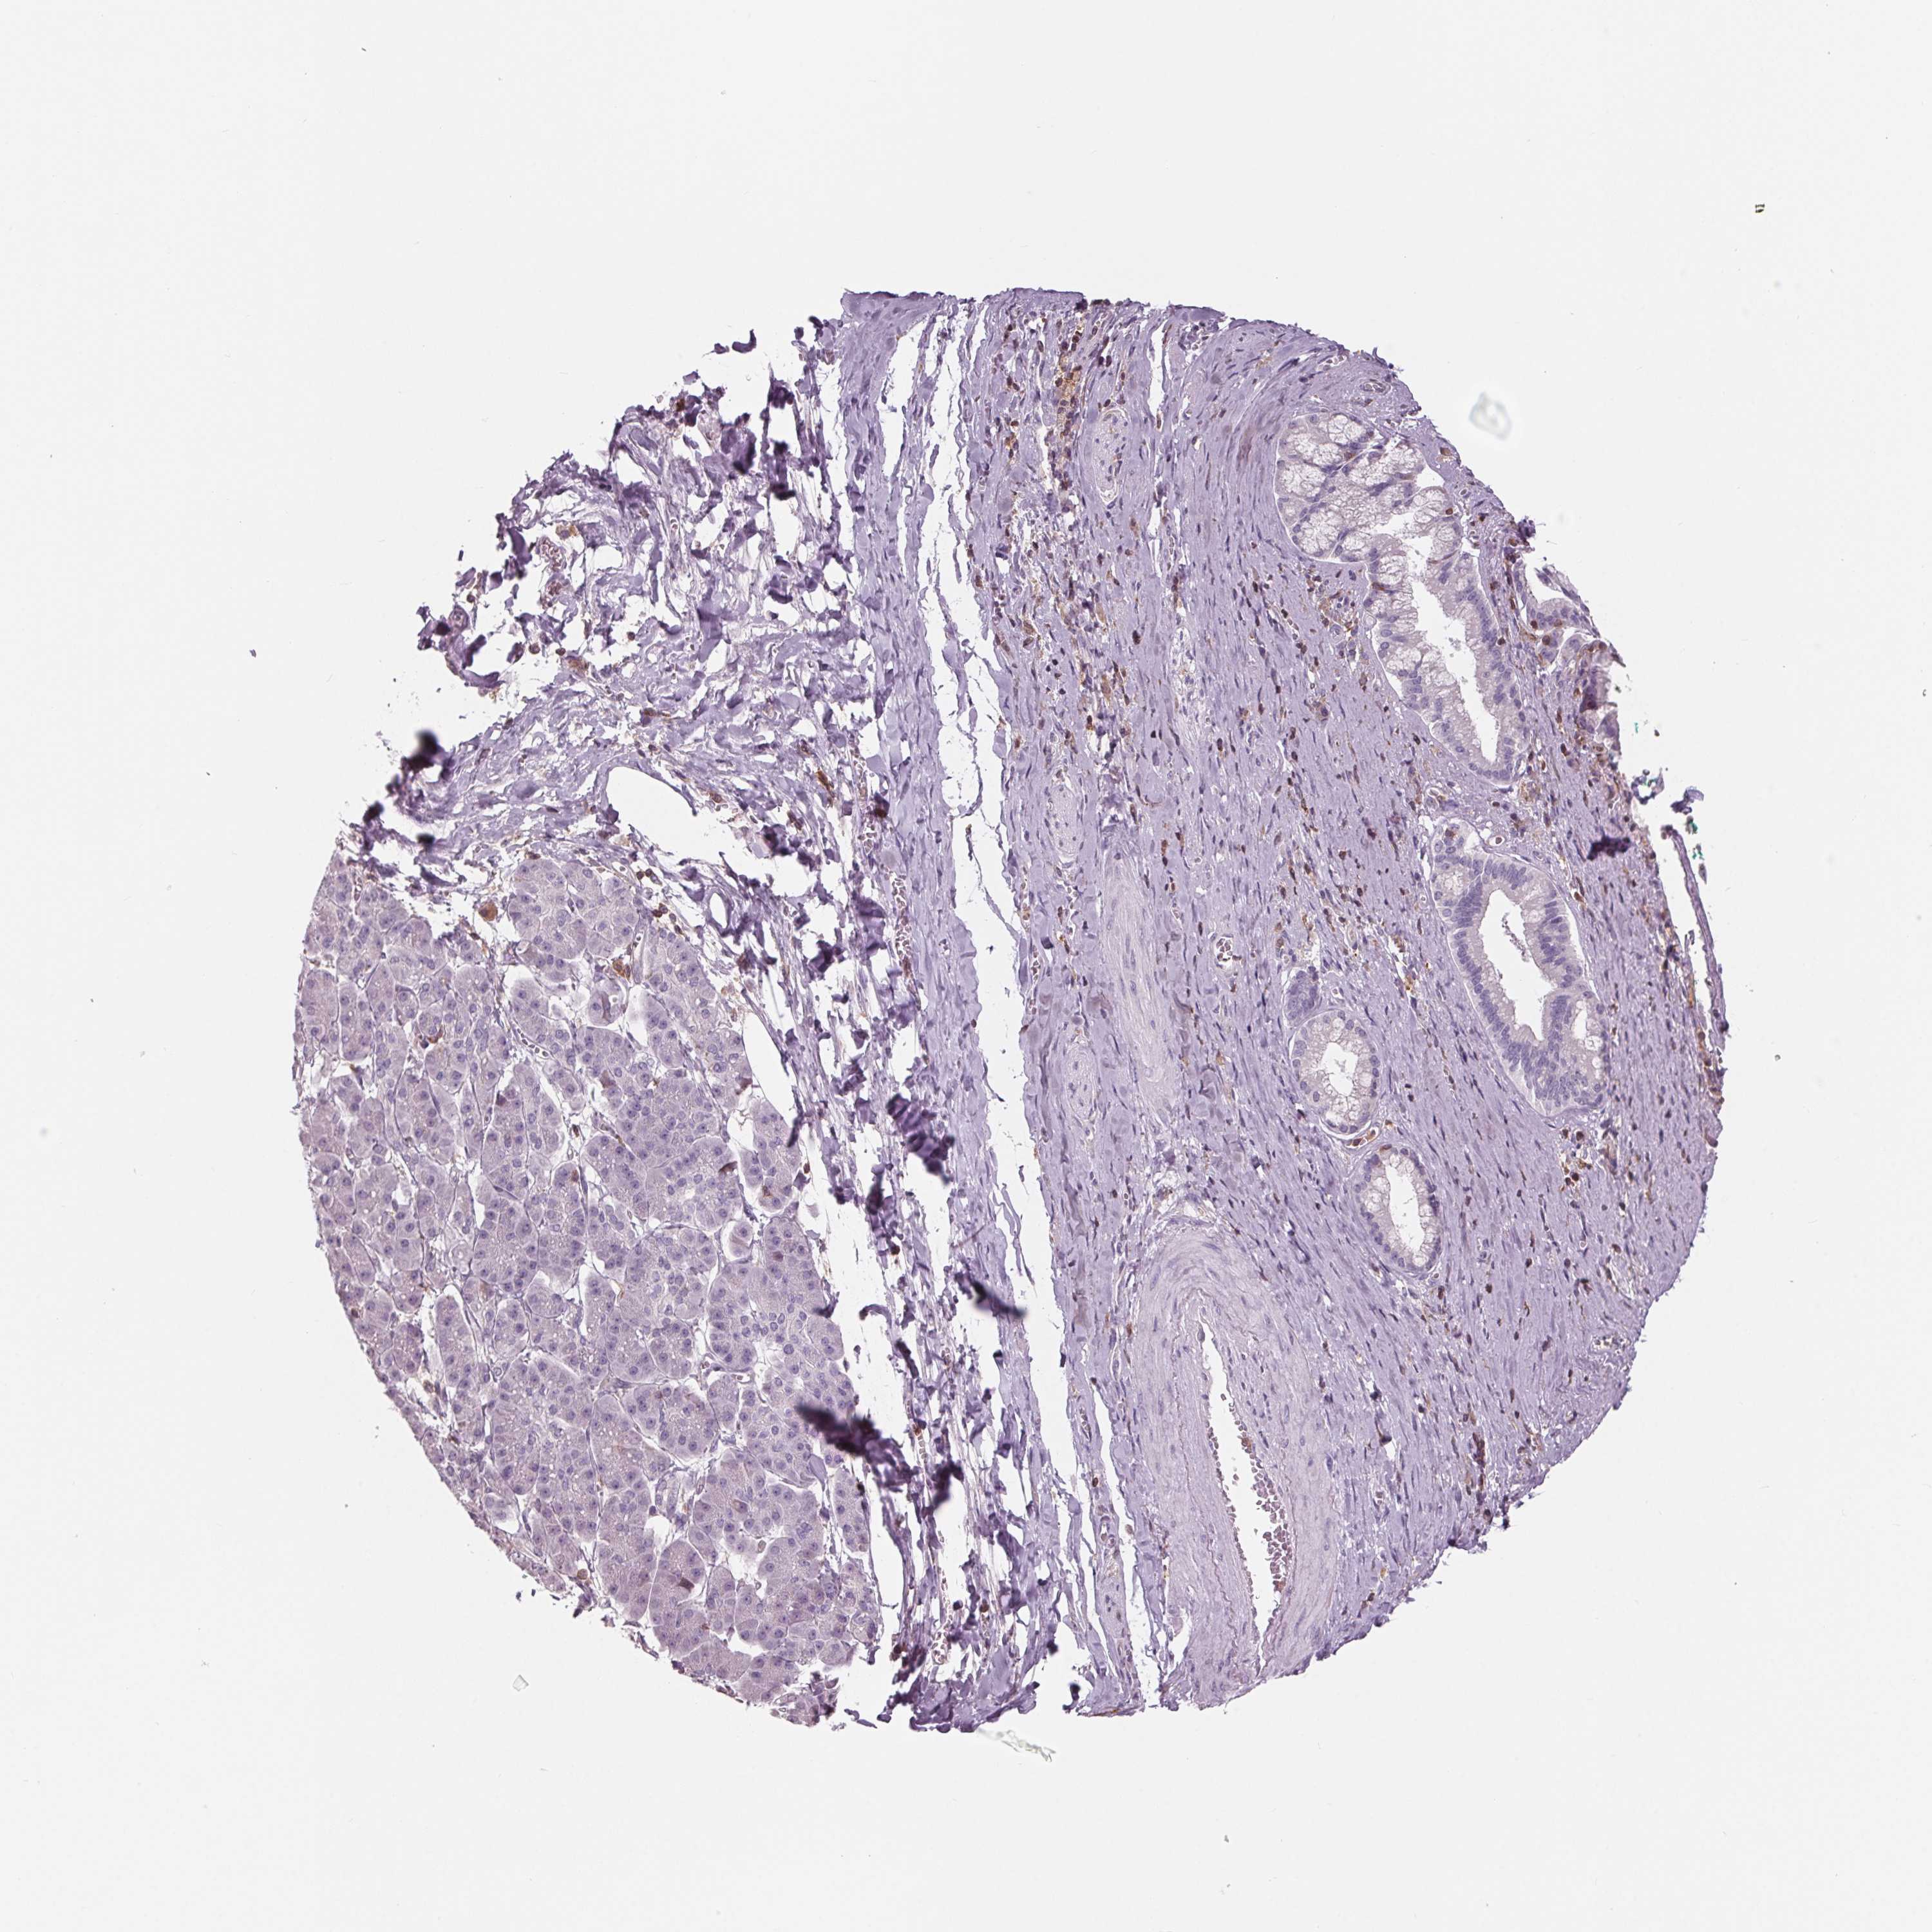

PANCREATIC CANCER - Protein expressioni

A mouse-over function shows sample information and annotation data. Click on an image to view it in a full screen mode. Samples can be filtered based on level of antibody staining by selecting one or several of the following categories: high, medium, low and not detected. The assay and annotation is described here.

Note that samples used for immunohistochemistry by the Human Protein Atlas do not correspond to samples in the TCGA dataset.

Antibody stainingi

Antibody staining in the annotated cell types in the current human tissue is reported as not detected, low, medium, or high, based on conventional immunohistochemistry profiling in selected tissues. This score is based on the combination of the staining intensity and fraction of stained cells.

Each image is clickable and will lead to virtual microscopy that enables deeper exploration of all samples and also displays staining intensity scores, fraction scores and subcellular localization as well as patient and tissue information for each sample.

Antibody HPA035346

Antibody HPA061395

Staining

High

Medium

Low

Not detected

Intensity

Strong

Moderate

Weak

Negative

Quantity

>75%

75%-25%

<25%

None

Location

Nuclear

Cytoplasmic/membranous

Cytoplasmic/membranous,nuclear

Adenocarcinoma, NOS